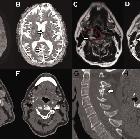

Chronic

fusiform extracranial vertebral artery aneurysm with recurrent posterior circulation emboli: Case report and review of the literature: A and B: Multiple foci of restricted diffusion (white arrow), with corresponding low ADC value in the posterior circulation involving the right occipital lobe, left thalamus and cerebellum (not shown), in keeping with acute embolic infarction. Older non-restricting foci of embolic infarction were also evident on T2 sequences (not shown). C: T2 weighted sequence of the neck at the C4 vertebral level demonstrating an abnormal right vertebral artery (red broken line) with a central flow void and abnormal circumferential thick mixed T2 signal material (white arrow). Maximal diameter of the fusiform aneurysm was up to 35mm. D: T2 weighted sequence of the neck at the C4 vertebral level five years prior to presentation confirming significant growth (white arrow) of the right vertebral artery (red broken line). E and F: CT angiography demonstrated a grossly abnormal right vertebral artery measuring up to 5cm in diameter. The aneurysm demonstrated thick thrombus lining the lumen (black arrow) with areas of fissuring and crenulation. The contralateral left vertebral artery was of normal calibre and appearances (white arrow). G: Sagittal bone window reconstruction of CT demonstrates abnormal appearance to the spinous processes (white arrow) of C2 to C4 consistent with historic trauma. H: Axial CT at C3 level shows a grossly expanded right foramen transversarium consistent with a chronic process of fusiform aneurysm formation (black arrow).